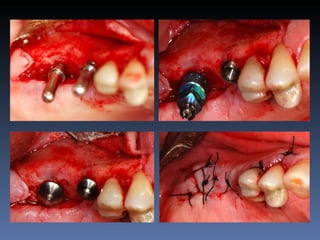

BOX 4

Maurício Zanetti

Idade – 47 anos

Sexo – Masculino

Raça – Caucasiana

ASA – II

Data- 25-04-2012

Diagnóstico: Desdentado parcial

pré-maxila.

Plano de tratamento: Reabilitação pré-maxila com

instalação de 2 implantes endo-ósseos (1.1,.2.2), para

reabilitação protética fixa.